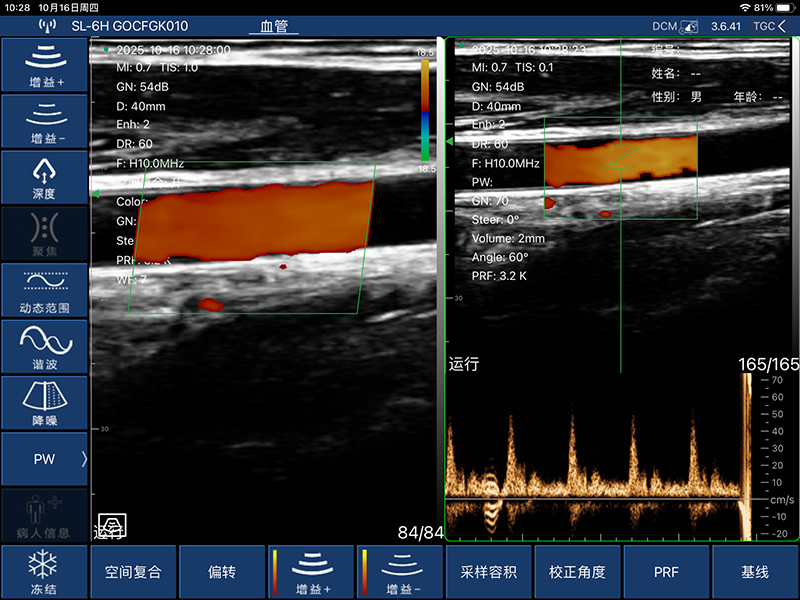

• 显示模式:B、B/M、Color、PW、PDI

• 扫描方式:电子阵列扫描

• 探头频率:7.5/10MHz

• 扫描深度:20-100mm,可调